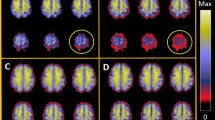

Image analysis

After PVC was performed, the boundary of gray matter, white matter and cerebrospinal fluid (CSF) was strengthened, as shown in Fig. 2.

We first visualized the network matrices to observe the differences of network structure after PVC. The BrainNet Viewer was used for the visualization (http://www.nitrc.org/projects/bnv/)51. After PVC, some inter-regional edges were recovered on all groups (please refer to Fig. 4 for an example of NC group), which indicated that PVC may reveal information of brain connectivity.